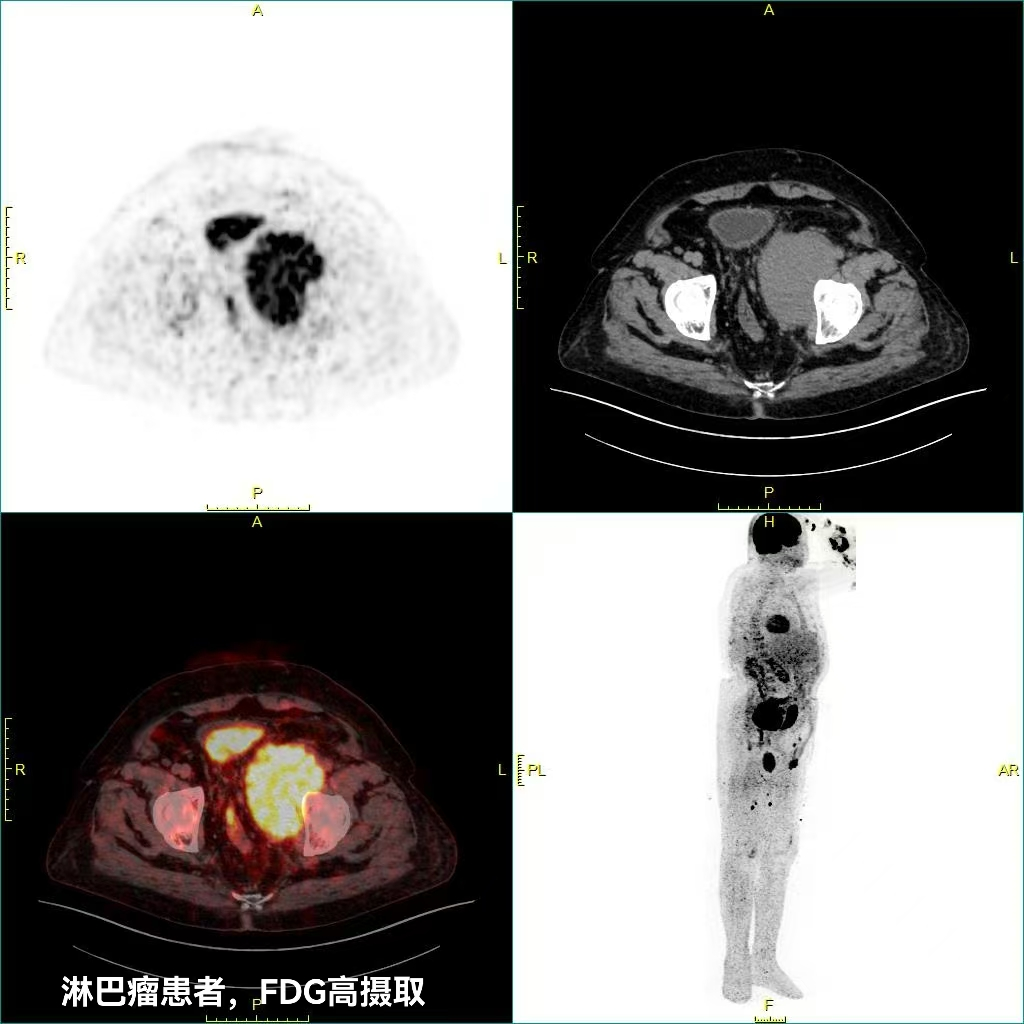

本次投入使用的核心设备为 PET-CT,采用联影全息数字技术,具备全身 13 分钟快速成像、图像高清低噪、超低剂量扫描等显著优势。核医学科主任徐玉波介绍,与传统影像设备相比,PET-CT 可同时实现解剖结构显像与功能代谢显像,能够更早发现微小病灶、更准确判断病变性质,在肿瘤筛查、分期、疗效评估等方面具有独特优势,为临床诊断与治疗方案制定提供重要支撑。

2.PET-CT。PET-CT 是核医学科的核心设备,将 PET 功能代谢显像与 CT 解剖结构显像相结合,一次扫描即可同时获取病灶位置、形态、大小及代谢信息,具有成像快、图像清、剂量低、诊断全面等优点。

(一)肿瘤相关应用

1.鉴别肿瘤良恶性,指导精准活检;

2.恶性肿瘤临床分期,辅助制定治疗方案;

3.放化疗、靶向治疗疗效早期评估;

4.肿瘤治疗后残留、复发鉴别;

5.寻找转移灶的原发肿瘤部位;

6.辅助放疗靶区勾画与计划制定;

7.肿瘤高危人群早期筛查。